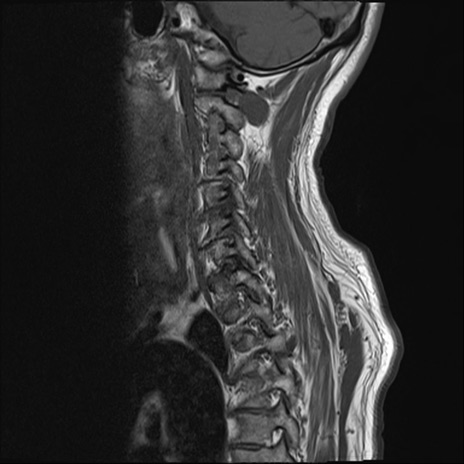

【整形】TIPS症例7 頚椎MRI T1WI(矢状断像)

頚椎MRI

T2WI(矢状断像)

矢状断像と横断像